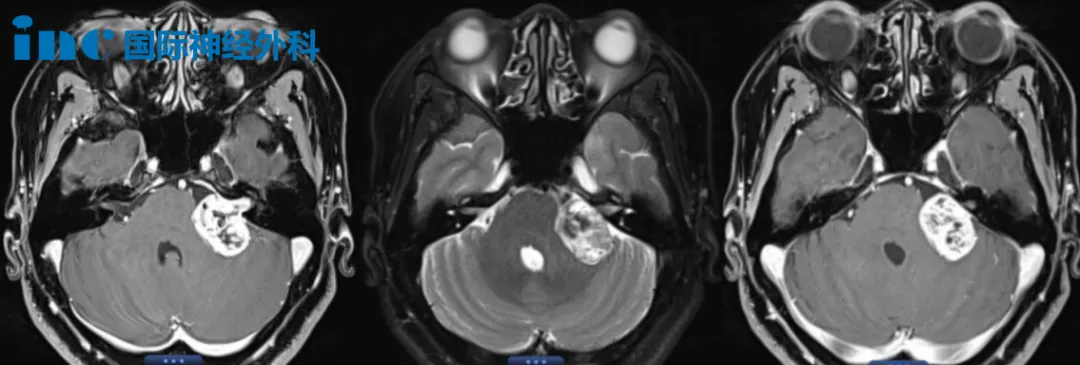

52歲女性-左側(cè)較大聽神經(jīng)瘤

52歲女性-左側(cè)較大聽神經(jīng)瘤案例圖片

52歲的江女士,較大的聽神經(jīng)瘤已經(jīng)壓迫面聽神經(jīng)及小腦。頭暈、步態(tài)不穩(wěn)、左側(cè)耳疼、耳鳴、聽力下降等嚴(yán)重癥狀嚴(yán)重影響到她的生活和工作。手術(shù)風(fēng)險(xiǎn)較大,這一次終于等到巴教授。江女士相信強(qiáng)強(qiáng)聯(lián)合,定會(huì)為她解決困境。面對(duì)巴教授的鼓勵(lì),她舉起拳頭,鏗鏘有力地說:“加油!加油!”而丈夫也一直在旁邊溫柔的撫著她的肩膀,給她力量。對(duì)于江女士關(guān)心的面癱問題,術(shù)前談話中,巴教授也為她再次詳細(xì)解答。